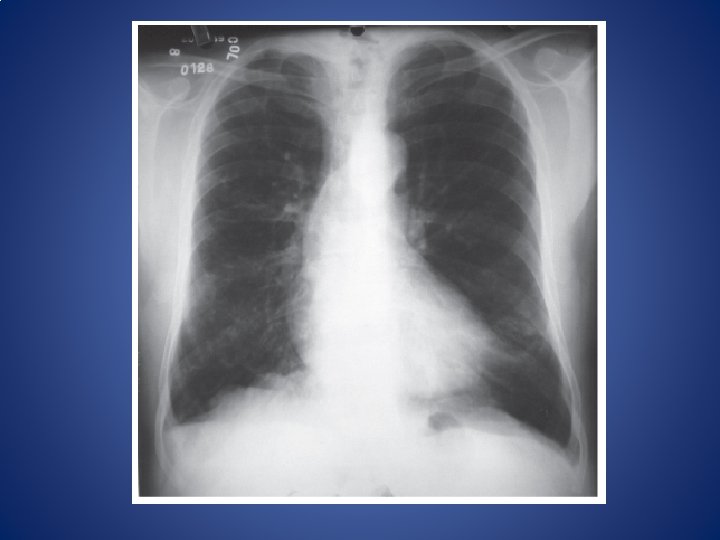

CASO CLÍNICO Paciente masculino de 14 años, diagnóstico de asma bronquial desde los 7,

CASO CLÍNICO Paciente masculino de 14 años, diagnóstico de asma bronquial desde los 7, los intervalos entre crisis cursa asintomático. Durante el cambio estacional, acude por que refiere dificultad para respirar, sobretodo en la noche y que el pecho le “silba y ronca”. • a. Mecánica ventilatoria normal. Presiones en el sistema respiratorio. Volúmenes pulmonares • b. Vías aéreas: anatomía. Espacio muerto. Inervación autonómica • c. Asma bronquial. Fisiopatología: fenómeno inflamatorio (mediadores químicos y células participantes). Signos y síntomas. Espirometría. Gases en sangre • d. Fármacos broncoconstrictores y broncodilatadores